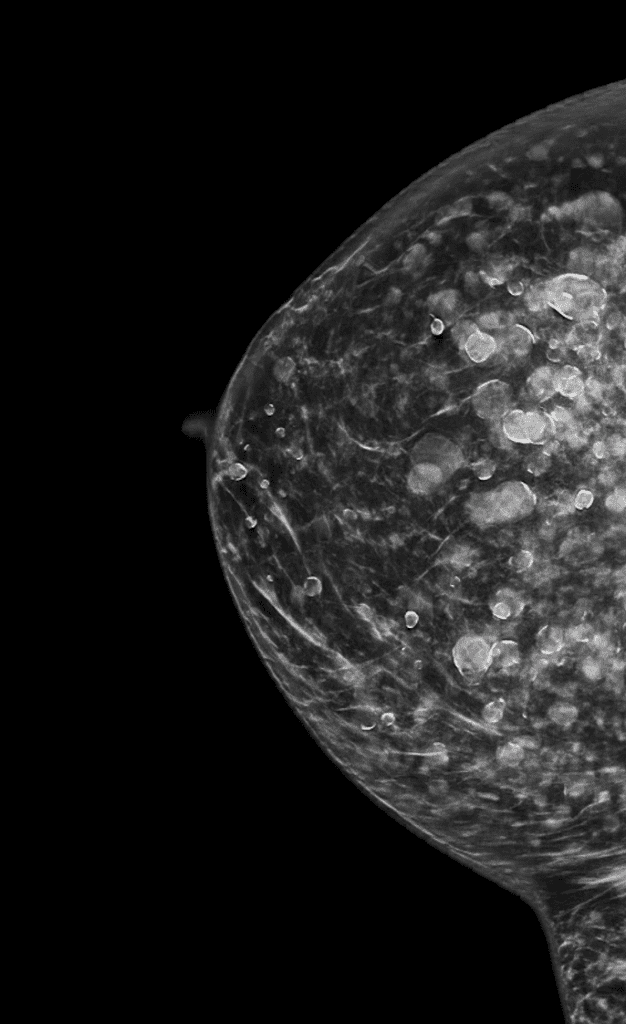

Silicone injection appearance on mammogram. This patient breastfed without issue.